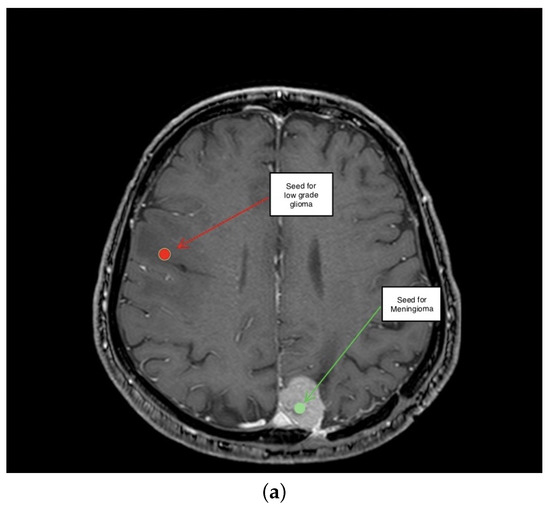

2. Description of the Methodology

3.3. Third Scenario